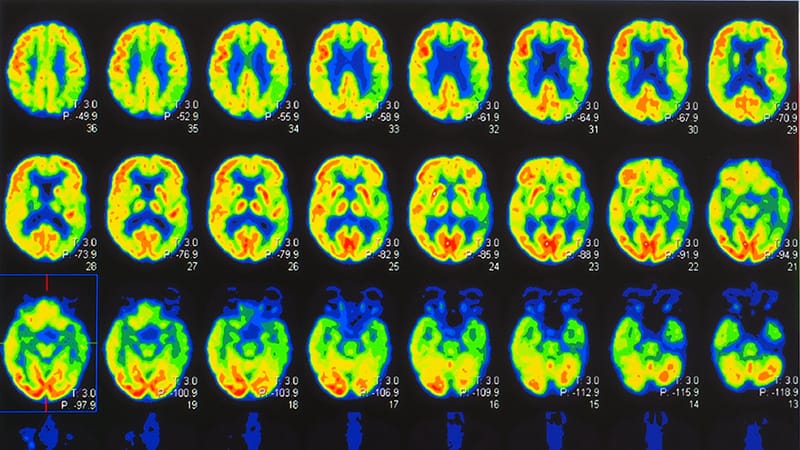

Bipolar Depression in Adolescents and Young Adults: A Disorder of Mind and Body -

Launching From an Unstable Platform: Bipolar Depression in Adolescents and Young Adults